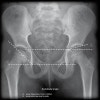

5. Hip Frog legs view

- Femur AP view

- Femur Lateral view